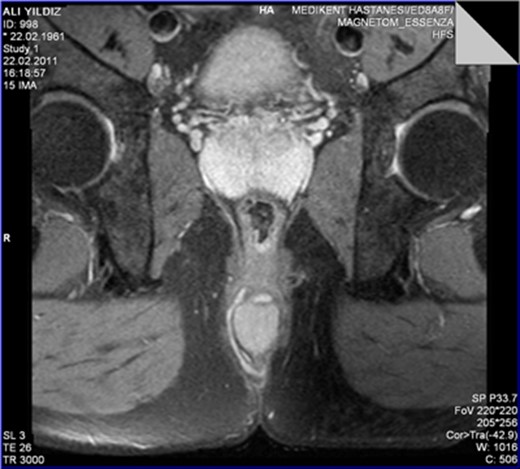

The MRI scan revealed a well-circumscribed homogeneous mass ovoid in shape, measuring 3.4 × 3.5 × 2.7 cm3 in diameter located in the intersphincteric plane, originating from the posterior aspect of the internal anal sphincter just in the midline, growing away from the lumen, displacing and stretching the external anal sphincter (Figs 1 and 2).

The leiomyoma originating from the internal anal sphincter growing far from the lumen stretching and pushing away the external anal sphincter.

The perinal fistula passing intersphincterically upwards in close relation to the leiomyoma without invasion.

T2A weighed MR sequences showed moderate to low signal intensity, and in post-contrast series there was no internal contrast uptake, necrosis, lymphadenopathy or cystic component. The perianal fistula was intersphincter, fistula tractus passing cranially and very close to the right lateral border of the mass without showing any sign of invasion. During surgery internal orifice of the fistula was identified at the level of dentate line. A stylet was passed through the fistula tractus which was confirmed to be intersphincteric and to be directed cranially in close relation to the right lateral border of the lesion without any signs of invasion. Fistulotomy is performed, dissection was performed meticulously without interruption of the pseudocapsule of the mass, and commenced up to the level where the mass was originating from internal anal sphincter. A few muscle fibers were carefully included into the specimen in order to preserve the integrity of the pseudocapsule and leave the anal sphincter intact. Histopathological examination showed fascicles of uniform spindle cells, with abundant eosinophilic cytoplasm, lack of nuclear atypia, lack of necrosis and practically inexistent mitotic activity (<1 mitoses/50 high power fields). The immunohistochemistry analysis showed a strong positivity for desmin and alpha smooth muscle actin and was negative for S100, CD117 and CD34 stains. This pattern is compatible with the diagnosis of leiomyoma. Postoperative course was uneventful. No complaints of anal incontinence were described by the patient. Patient is now symptom free for 8 years of follow-up.